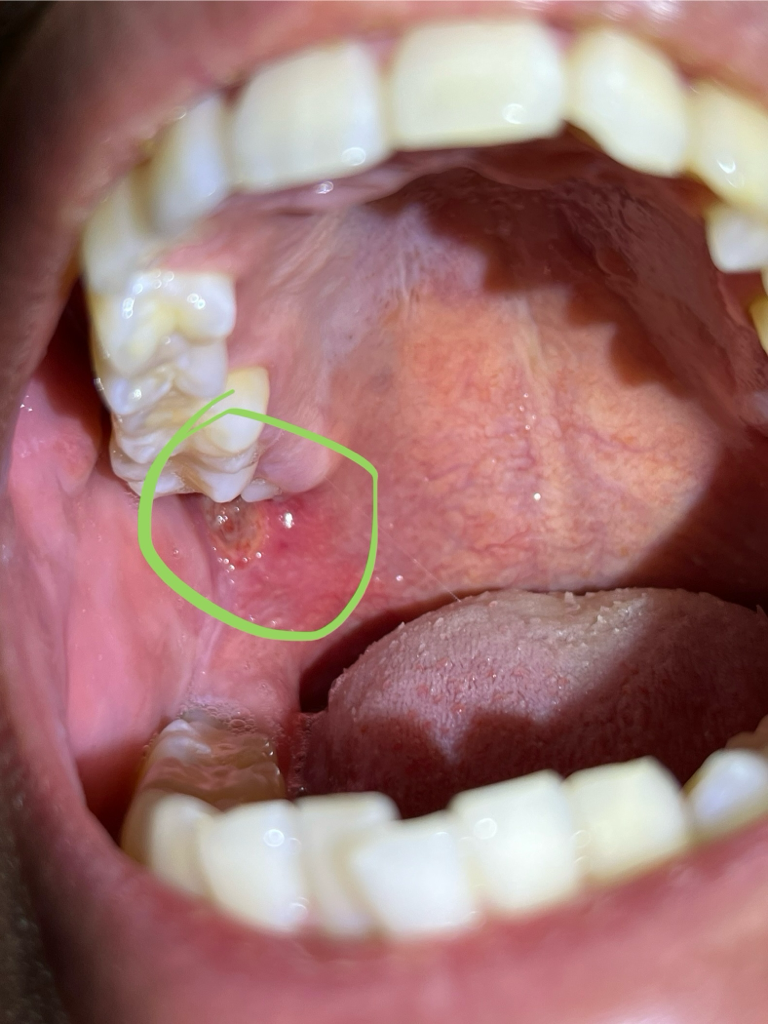

사진상으로는 구내염으로 보입니다. 증상이 사그라들면 지켜보시고 심해지면 치과 가보시는게 좋습니다.

구내염이 생기신거 같습니다. 일단 치과에 가셔서 일단 염증치료를 받아보시는게 좋을것같습니다.

아프타성 구내염 또는 상악사랑니의 물리적 자극에 의한 손상 둘 중 하나일 가능성이 높습니다.

일단 해당 병소가 2주 이내에 없어지지 않으시면 대학병원에 가보시길 바랍니다.

2주 이내에 해당 병소가 사라지면 별것 아닙니다.

해당병소에서 출혈이 되거나 통증이 심하시면 오히려 별것이 아닐 수 있습니다.